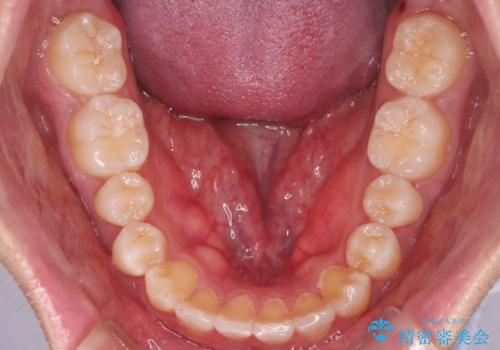

- 上の歯が出ているのが気になるのを主訴にご来院されました。人前で話すお仕事をされており目立たないマウスピース治療を希望されていました。

口元のEラインは気にならないとのことだったのでインビザラインにて治療していくことにしました。

IPR(歯と歯の間を削る処置)と歯列拡大をすることで前歯を少し下げ、がたつきを改善していく治療計画を立てました。

上の前歯が出ているという主訴が綺麗に改善されました。

その他の部位のがたつき、奥歯の噛み合わせも以前と比べると良くなっています。